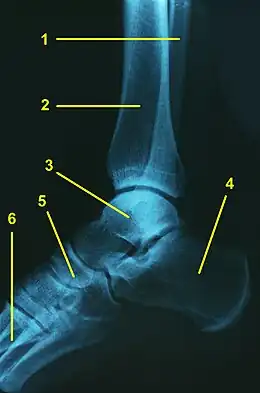

L'articulation talo-crurale (ou articulation tibio-astragalienne ou articulation tibio-tarsienne ou articulation du cou-de-pied ou articulation de la cheville) est l'articulation trochléenne qui unit le pied à la jambe au niveau de la cheville.

L'articulation talo-crurale est formée par les extrémités distales du tibia et de la fibula formant un ensemble tenon - mortaise avec le talus. Les deux os de la jambe forment ensemble une mortaise qui enserre le tenon formé par le talus.

L'articulation talo-crurale met en jeu :

Ces trois facettes formant la pince de la mortaise.

La surface articulaire au niveau du tenon étant formée par la trochlée du talus.

Ligament collatéral médial de l'articulation talo-crurale, ligament collatéral latéral de l'articulation talo-crurale, facette articulaire de la malléole médiale du tibia (d), surface articulaire inférieure du tibia (d), facette articulaire de la malléole latérale (d), trochlée du talus (d)